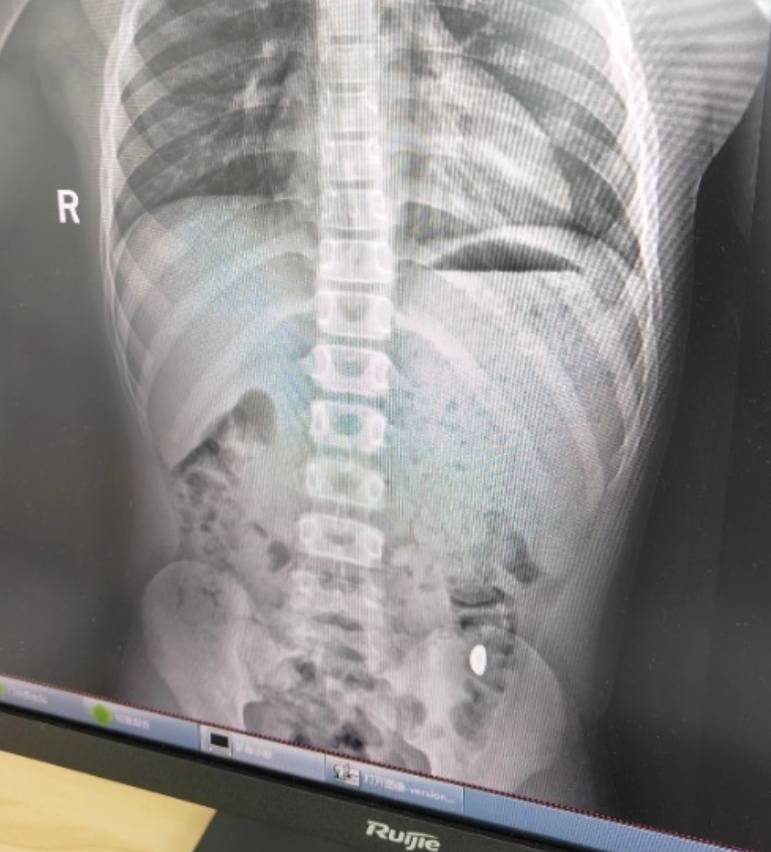

右下加亮点为金豆ERC20。